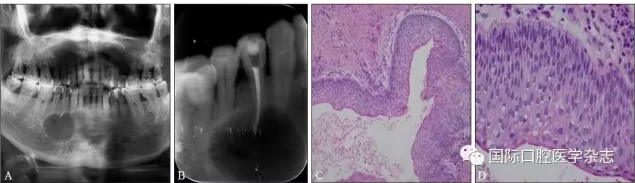

典型病例3 患者右下頜長包1月,臨床初診為44牙根尖周囊腫,治療期間反復(fù)換藥,伴右下頜脹痛,根管充填后轉(zhuǎn)診外科行根尖囊腫刮治A術(shù),術(shù)后病理示:右下頜骨KCOT伴感染(圖3)。

A:術(shù)前全景片,43—45根方透射影像,邊緣可見骨白線;B:術(shù)前充填根尖片;C、D:蘇木精-伊紅染色切片,示腫瘤襯里上皮表面為波浪狀的不全角化層,基底層細(xì)胞柵欄狀排列,細(xì)胞核遠(yuǎn)離基底膜,C圖 × 100,D圖 × 400。

圖 3 右下頜骨KCOT